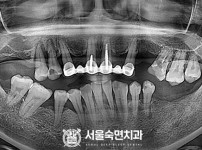

임플란트-전후사진2

치과를-선택할-때-꼭-확인하세요-서울숙면치과-임플란트-전후사진